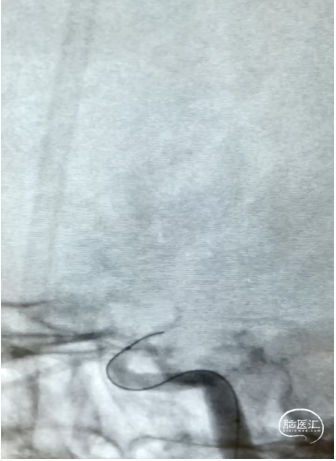

2、颈内动脉正侧位造影

3、微导丝通过闭塞段

4、微导管造影、交换Transend 300

5、2.5mm x 15mm Gateway成形

6、3mm x 10mm APOLLO成形